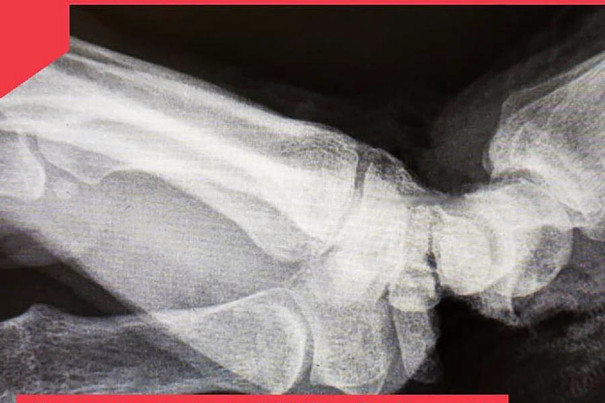

Сотруднице одного из владимирских предприятий ножом для резки пленки отсекло кисть в области соединения с предплечьем правой руки.

В результате несчастного случая кисть была практически оторвана и держалась только на маленьком кусочке кожи. Сосуды, нервы, сухожилия и основная часть мягких тканей были отрезаны.